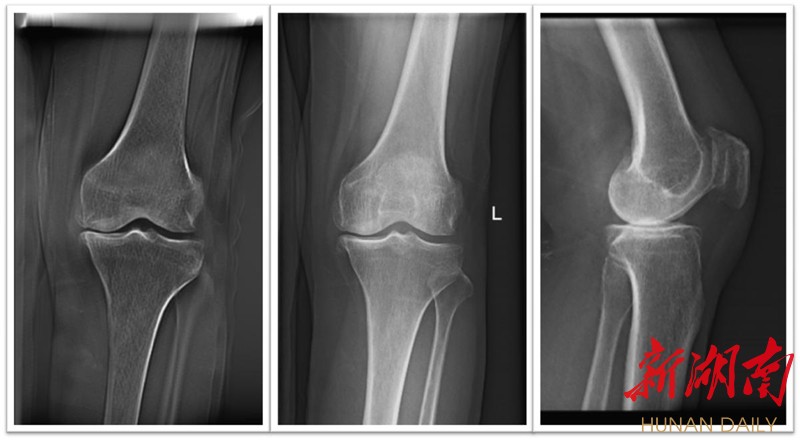

术前膝关节正侧位片